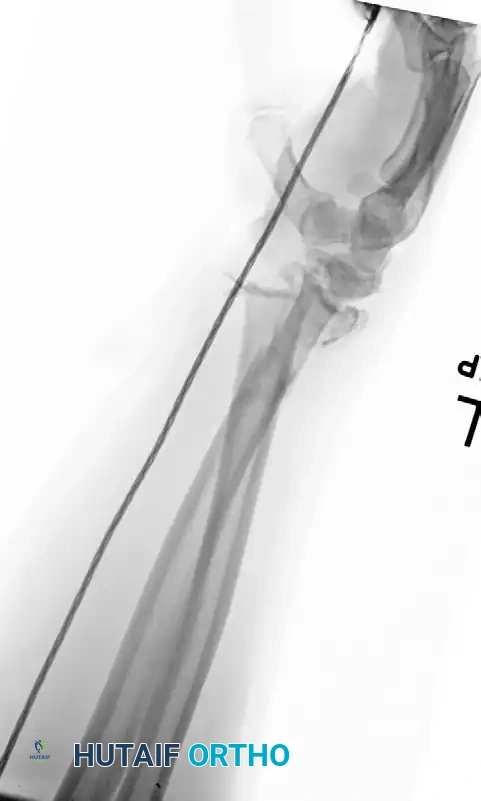

Figure 57-82C: Postoperative AP radiograph demonstrating anatomical reduction and rigid fixation with 3.5-mm compression plates.

Figure 57-82D: Postoperative lateral radiograph confirming restoration of alignment and appropriate plate contouring.